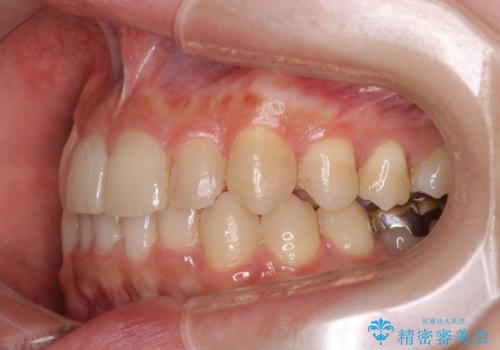

奥歯を後方に移動することで、歯を抜かずに矯正を終えることができました。